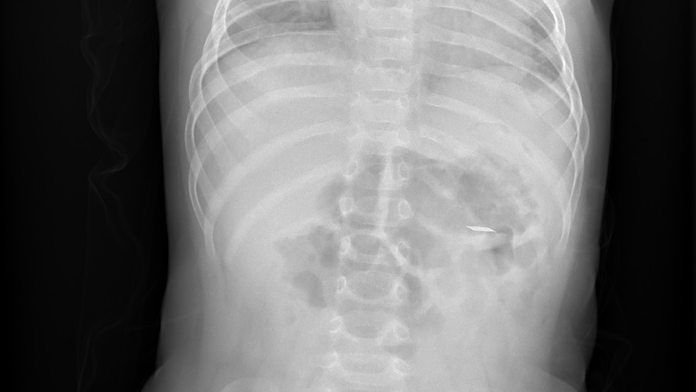

Nemocnica varuje rodičov. Viacero batoliat prehltlo ostrý pliešok z e-cigariet, môže ich vážne zraniť

Deti prehĺtajú pliešky Zdroj: Nemocnica v Motole

Lekári z českej nemocnice Motol varujú rodičov. Riešili už desať prípadov, kedy batoľa zjedlo malú a ostrú kovovú časť, ktorá je súčasťou cigariet do elektronických zariadení na zahrievanie tabaku.

V uplynulom roku hospitalizovali v pražskej nemocnici desať detí od ôsmich do pätnástich mesiacov, ktoré tento kovový pliešok prehltli.

„U troch malých pacientov sme museli vykonať urgentný endoskopický zákrok, v ďalších prípadoch boli deti sledované počas hospitalizácie, kým cudzí predmet neodišiel sám. Kovový pliešok má ostré hrany a môže spôsobiť poškodenie tráviaceho traktu, v najhoršom prípade môže dôjsť aj k prederaveniu,“ upozorňuje doktorka Kristýna Zárubová z oddelenia detskej gastroenterológie.

Vďaka rýchlej lekárskej intervencii sa v každom prípade podarilo zabrániť potrebe chirurgického zákroku.